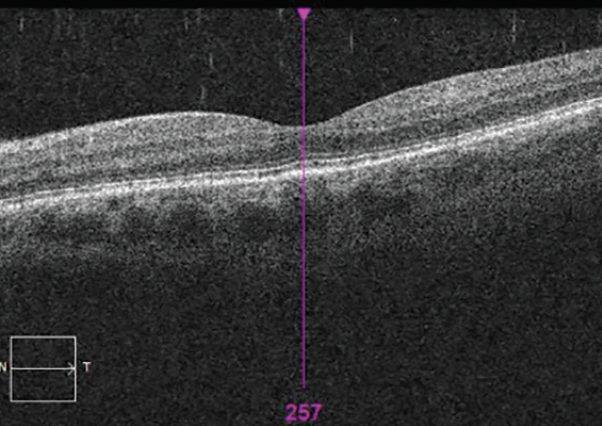

Spectral-domain OCT showed irregularity and thickening of the retinal pigment epithelium (RPE) layer, hyper-reflectivity of the outer nuclear layer, and obliteration of the outer limiting membrane in the macular region of each eye. The macula OD also showed evidence of subretinal fluid (SRF) at the fovea (Figures 4 and 5).

<p>Figure 5. OCT showing irregularity and thickening of the RPE and obliteration of outer limiting membrane in the macular region OS.</p>

Figure 5. OCT showing irregularity and thickening of the RPE and obliteration of outer limiting membrane in the macular region OS.